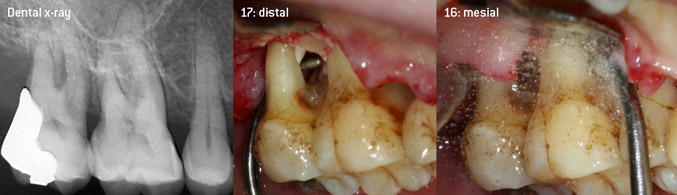

En tant qu'initiateurs du développement du nouvel insert détartreur à air N° 3AP avec un revêtement diamant, les deux dentistes ont reconnu la nécessité d'améliorer les restrictions de manipulation des inserts avec un revêtement diamant disponibles dans le commerce, en particulier lors du traitement des furcations et du travail dans des poches intra-osseuses étroites. Cela devrait être possible pour les procédures non-chirurgicales (figure 2) et chirurgicales (figure 3).

(Photos (Figures 2-4): © Dr. Christian Graetz)